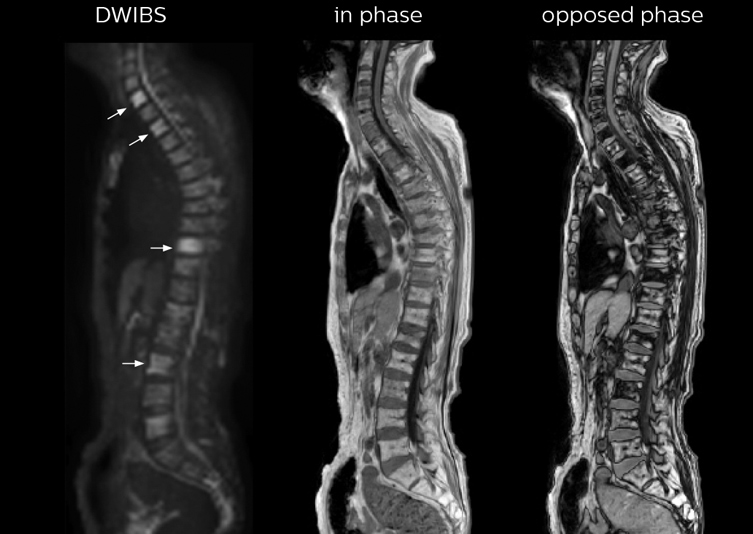

“The DWIBS sequence’s value in oncology cases is due to the high contrast it creates between lesions and surrounding tissue. Whole body DWI is requested by physicians who need to clarify TNM staging or determine therapeutic strategies, oncologists in need of diagnosis or follow-up scans, surgeons who need to see the presence of distant lesions that are sometimes difficult to detect by CT before surgery, and urologists for the evaluation of bone lesions, and the effect of chemotherapy and radiotherapy.”

“In-phase and out-phase sagittal T1-weighted FFE images help us to visualize and further characterize bone lesions such as metastasis and bone-marrow hyperplasia that have high signal on DWI. These images are also used throughout radiotherapy, to monitor changes in the fatty bone marrow.”

After implementing the improved whole body protocol, the radiology team initially did not see a large increase in referrals, although Dr. Nobusawa saw clinical cases where the DWIBS images provided him valuable information for diagnosis. This is why Dr. Nobusawa and Mr. Naka started to actively educate referring physicians about the value of whole body DWIBS. They organized several presentations for physicians in the hospital, where they explained how DWIBS can be of value in oncology patients. The information it provides can be useful for physicians when staging cancer, as well as when determining or adjusting treatment strategy. Mr. Naka remembers some cases where DWIBS provided remarkable information. “In one example, DWIBS visualized bone lesions that could not be seen on PET or SPECT. In another case we had found a bone lesion when a normal L-spine scan for narrowing of the disk space was done. One extra DWIBS scan (2 stations, 8 minutes) demonstrated a lesion that later was confirmed to be the primary region of cancer.”